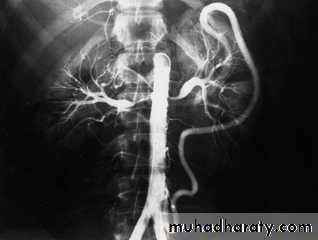

Angiogram showing bilateral renal artery stenosis.